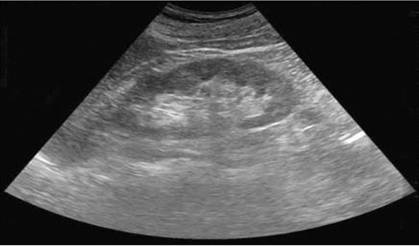

Основним доступом при локації нирок є бокове розташування датчика по середній пахвовій лінії. Дана проекція дає зображення нирки, порівнянне з зображенням при рентгенологічному дослідженні. При скануванні по довгій осі органу нирка має вигляд овального освіти з чіткими, рівними контурами (додаток 1).

Поліпозиційне сканування з послідовним переміщенням площині сканування дозволяє отримати інформацію про всі відділи органу, в якому диференціюються паренхіма і центрально розташований ехокомплекс. Кортікальний шар має рівномірну, кілька підвищену в порівнянні з мозковою речовиною ехогенність. Мозкова речовина, або піраміди, на анатомічному препараті нирки мають вигляд трикутних структур, звернених підставою до контуру нирки і вершиною до порожнинної системі. У нормі видима при УЗД частина піраміди складає близько третини від товщини паренхіми [19].

У формуванні зображення центрального синуса беруть участь такі анатомічні структури, як елементи порожнинної системи, судинні освіти, лімфатична дренажна система, жирова тканина. У здорових людей під час відсутності водного навантаження елементи порожнинної системи, як правило, не диференціюються, можлива візуалізація окремих чашок до 5 мм. В умовах водного навантаження іноді візуалізується балія, як правило, вона має форму трикутника розміром не більше 15 мм.

Сонограма. Нормальна будова нирки